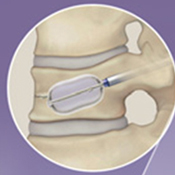

VBS

BKPと同様に細い筒から骨折したせぼねに風船をしぼめた状態で設置して、ゆっくり風船を膨らませます。風船でステントを広げてスペースを作り、風船を取り出してステントとともにセメントを注入します。